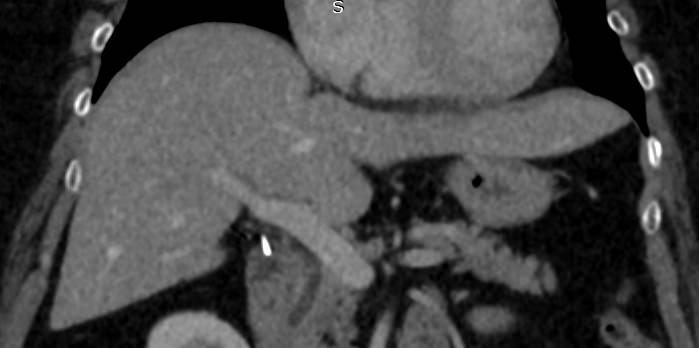

Мультиспиральная компьютерная томография с внутривенным болюсным контрастированием является наиболее точным и информативным методом диагностики патологии воротной вены. КТ основана на применении ионизирующего излучения и способности органов и тканей в разной степени поглощать рентгеновские лучи.

Для улучшения визуализации сосудистого русла пациенту внутривенно вводится йодсодержащий контрастный препарат. Рентгеновские лучи активно поглощаются контрастным веществом, поэтому на снимках хорошо видна сосудистая система воротной вены.

На снимках и трехмерных изображениях хорошо контрастируется сосудистая система воротной вены, участки сужения, визуализируются тромбы в просвете вены, также сеть коллатеральных сосудов, варикозно расширенные вены.